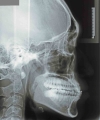

初診時